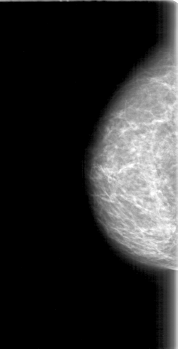

D_4069_1.LEFT_MLO

LEFT_CC LINES 4531 PIXELS_PER_LINE 2101 BITS_PER_PIXEL 12 RESOLUTION 43.5 OVERLAY

FILE: D_4069_1.LEFT_CC.OVERLAY

TOTAL_ABNORMALITIES 1

ABNORMALITY 1

LESION_TYPE MASS SHAPE LOBULATED MARGINS MICROLOBULATED

ASSESSMENT 0

SUBTLETY 3

PATHOLOGY BENIGN

TOTAL_OUTLINES 1

BOUNDARY